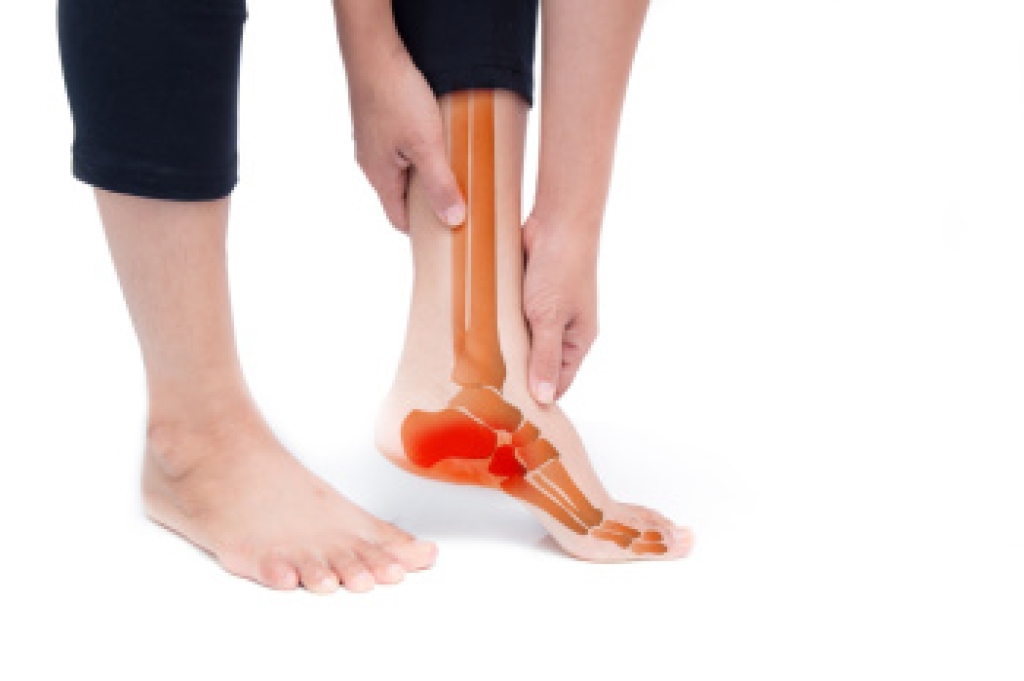

Rheumatoid Arthritis and Foot Health

Rheumatoid arthritis, or RA, is an autoimmune disease that causes inflammation in the joints. In RA, the immune system mistakenly attacks the lining of the joints, causing swelling, pain, and potentially severe joint damage. This can cause problems in any of the 30 foot joints, but it most commonly affects the toes and ankles. RA can also lead to deformities such as bunions, claw toes, or severe flattening of the foot, as well as pain and difficulty walking. Chronic inflammation can weaken the ligaments and tendons in the foot, leading to instability and increased risk of injury. Podiatrists, or foot doctors, can help manage RA-related foot issues by providing targeted treatments. Among them are orthotics to support the joints, advice on proper footwear to reduce stress on the affected areas, and exercises to maintain joint function and mobility. They also monitor for changes or deterioration in foot health that might require more aggressive interventions, including injections or surgery. If you’re a rheumatoid arthritis patient with problems in the feet and ankles, it is suggested that you add a podiatrist to your care team.

What Is Rheumatoid Arthritis?

Rheumatoid Arthritis (RA) is an autoimmune disorder in which the body’s own immune system attacks the membranes surrounding the joints. Inflammation of the lining and eventually the destruction of the joint’s cartilage and bone occur, causing severe pain and immobility.

Rheumatoid Arthritis of the Feet

Although RA usually attacks multiple bones and joints throughout the entire body, almost 90 percent of cases result in pain in the foot or ankle area.